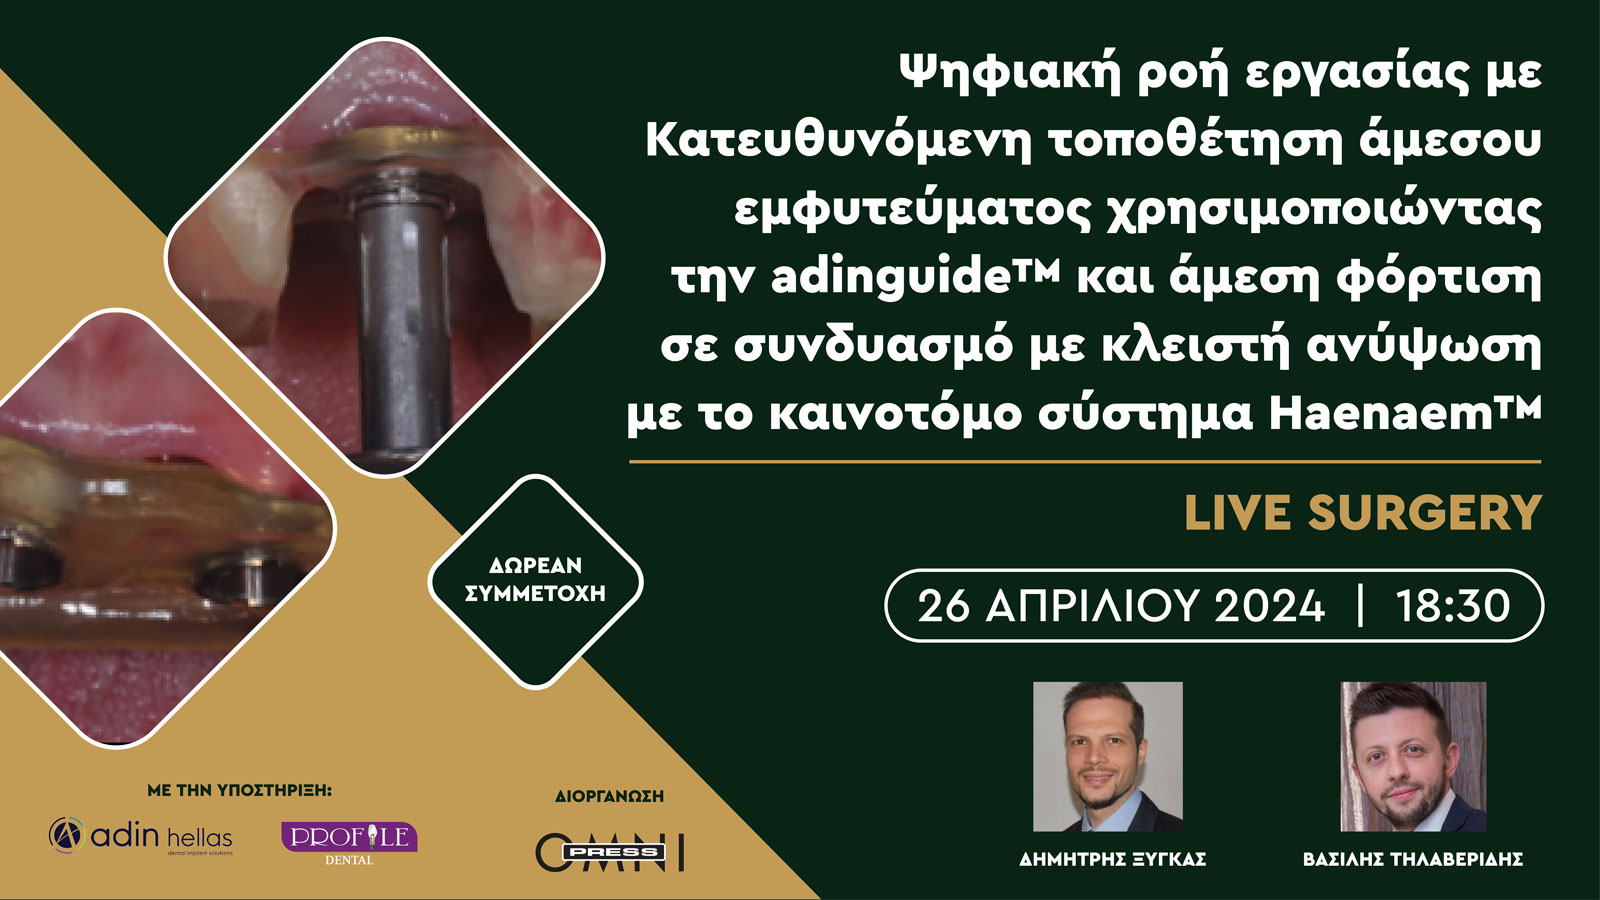

Τίτλος ομιλίας:

Guided Surgery Approach

Τηλαβερίδης Βασίλης

Τίτλος ομιλίας:

Κλειστή Ανύψωση Ιγμορείου με τη χρήση του kit της Haenaem

Σε αυτό το online σεμινάριο θα περιγράψουμε τις αρχές, τα πλεονεκτήματα και τα σημεία προσοχής της κατευθυνόμενης τοποθέτησης εμφυτευμάτων. Θα εξετάσουμε αρχικά πως μπορούμε να εκμεταλλευτούμε την ψηφιακή τεχνολογία με λήψη δεδομένων με αποτύπωση μέσω ενδοστοματικού σαρωτή (scanner) και αξονικής τομογραφίας κωνικής δέσμης (CBCT). ‘Επειτα, θα παρακολουθήσουμε πως μπορούμε να συνδυάσουμε τα δεδομένα (matching) ώστε να καταστρώσουμε ένα σχέδιο θεραπείας και σύμφωνα με αυτό να τοποθετήσουμε ψηφιακά τα εμφυτεύματα στην επιθυμητή θέση. Θα δούμε πως σχεδιάζεται ο νάρθηκας για την τοποθέτηση των εμφυτευμάτων, καθώς και η πιθανή προσωρινή εργασία για άμεση φόρτιση.

Στο live χειρουργείο θα γίνουν άμεσα εμφυτεύματα με τη βοήθεια χειρουργικού νάρθηκα για κατευθυνόμενη τοποθέτηση και άμεση προσωρινή αποκατάσταση με ταυτόχρονη λεπτομερή επεξήγηση των σταδίων και των πιθανών προβλημάτων και πως αυτά μπορούν να προληφθούν ή να αντιμετωπιστούν. Επίσης, θα γίνει σάρωση της περιοχής με scanner για την προετοιμασία της τελικής προσθετικής αποκατάστασης.